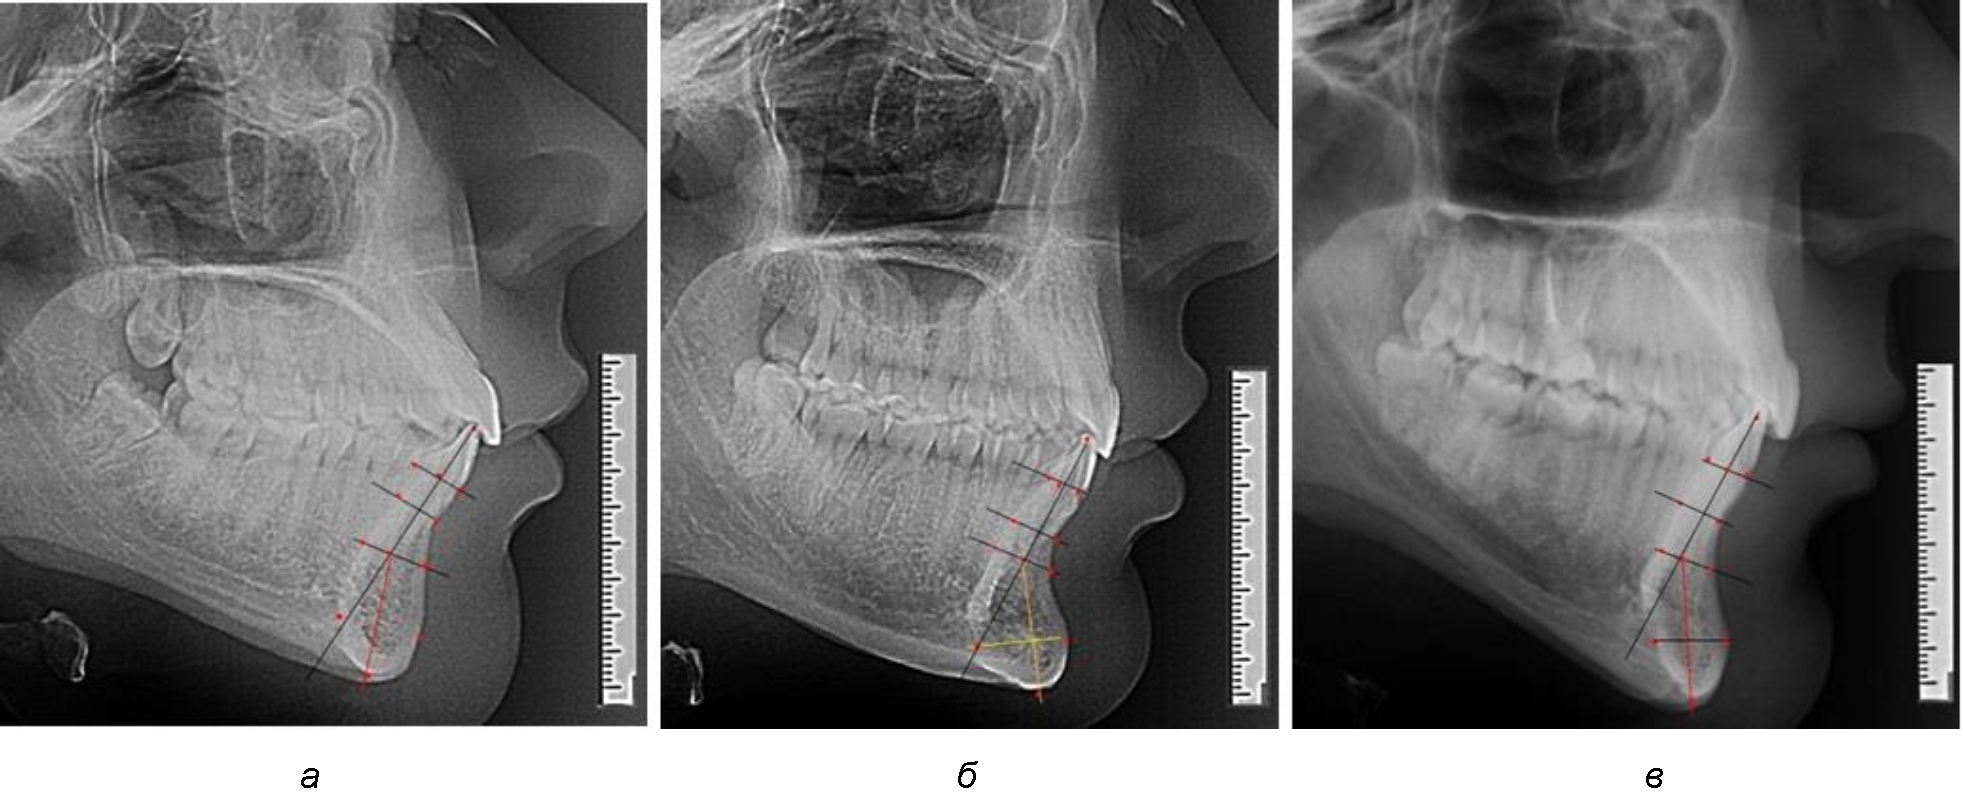

При анализе полученных данных обращает на себя внимание факт того, что из вертикальных параметров зубоальвеолярной части сегмента наиболее вариабельным является размер между апикальными точками Downs и Schwarz (BSM–B), который составлял (6,79 ± 0,54) мм, при величине сигмального отклонения – 2,35. Также большая ошибка репрезентативности и сигмальное отклонение было отмечено при оценки ширины подбородочного выступа. В связи с этим встречались варианты резцовых сегментов нижней челюсти различные как по ширине, так и по высоте, а также по расхождению положения апикальных точек по Downs и Schwarz (рис. 3).

Рис. 3. Варианты среднего (а), широкого (б) и узкого (в) нижнечелюстного резцового сегмента

Варианты резцовых сегментов нижней челюсти различные как по ширине, так и по высоте, а также по расхождению положения апикальных точек по Downs и Schwarz представлены на рис. 4.

Рис. 4. Особенности нижнечелюстного резцового сегмента на ТРГ у людей при среднем (а), широком (б) и узком (в) вариантах

Нередко отмечается деформация подбородочного выступа и различное его положение по отношению к зубоальвеолярной части сегмента. При мезиальной окклюзии нередко нижняя подбородочная точка смещается кзади по отношению к условной срединной вертикали нижнего резца, а при дистальной окклюзии отмечается компенсаторное отклонение подбородка кпереди (рис. 5).

Рис. 5. Особенности нижнечелюстного резцового сегмента на ТРГ у людей при мезиальной (а) и дистальной (б) окклюзии

Кроме того, так же как и у людей с физиологической окклюзией, определялось различие в положении апикальных точек Downs и Schwarz, что, по нашему мнению, может определять тактику лечения патологических форм протрузии/ретрузии резцов с учетом биотипа костной ткани.